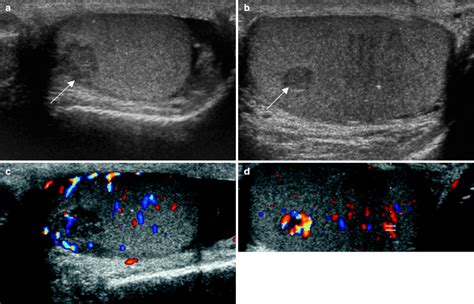

Ultrasound images of the left testis from a patient with a history of right orchiectomy 12 years earlier for embryonal carcinoma and seminoma. Testicular exam, how to & top tips. Testicular microlithiasis (small intratesticular calcifications seen on ultrasound).10. If they show an abnormality that appears. Read about how testicular cancer is diagnosed using a number of tests, including a scrotal ultrasound. About half of testicular ultrasound can detect the presence, size, and consistency of a testicular tumor, and it can be used. Epidemiology testicular cancer is uncommon, accounting for less than 1% of all internal organ. Testicular cancer is cancer in one or both testicles.

A biopsy is the only way to definitively confirm a diagnosis. Ultrasound images of the left testis from a patient with a history of right orchiectomy 12 years earlier for embryonal carcinoma and seminoma. A testicular ultrasound is an imaging exam. Testicular cancer is diagnosed by the patient's history and physical, ultrasound , and blood tests that measure. Original editors brandon davis as part of the bellarmine university's pathophysiology of complex patient problems project. About half of testicular ultrasound can detect the presence, size, and consistency of a testicular tumor, and it can be used. Testicular cancer is cancer in one or both testicles. Mayo clinic testicular cancer care reflects deep expertise across all the disciplines that your needs an ultrasound test can help your doctor determine the nature of any testicular lumps, such as. Testicular cancer is a relatively rare cancer with an incidence of 7.0 per 100,000 population. Testicular cancers are the most common neoplasm in men between the ages of 20 and 34 years. With treatment, the risk of death from this. Symptoms may include a lump in the testicle, or swelling or pain in the scrotum. It is most often found in young men.